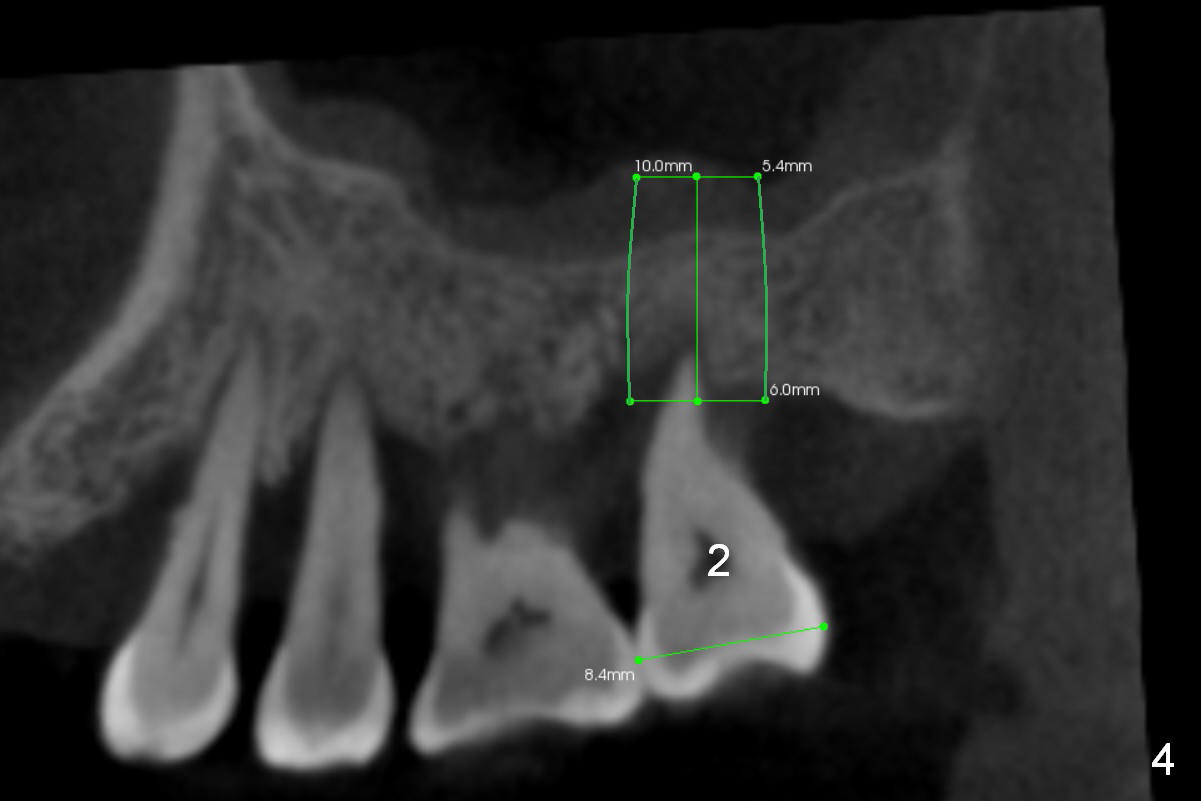

A 46-year-old lady is a typical dental phobic, but she is reasonable. Her chronic periodontitis is generalized and severe (Fig.1 3-D image, taken 1 year ago). An implant has been placed at #6 (healed site). It fails for the first time, probably due to bone loss after extraction. Soon after last periodontal maintenance, the tooth #2 develops pain and swelling. Immediate implant is a must.

The socket is wider buccopalatally (Fig.2 (3-D disto-occlusal view),3 (coronal section)) than mesiodistally (Fig.1,4 (sagittal section),5 (axial section)). Unless more bone loss has occurred in the last year, a 6x10 mm UF implant is to be placed in the middle of the socket (Fig.6, (soaked with 2% Xylocaine/1:50,000 Epinephrine gauze)) with bone graft to be placed in the buccal and palatal gaps (red circles). Bone density in the middle of the socket is 550-700 Hounsfield units. Use RT2 or 2 mm pilot drill to start osteotomy ~ 3 mm. The largest osteotome is RT4, or largest reamer 4 mm, followed by 4.5x17 mm tap at 14 mm, until 6x17 mm one. Make sure that the sinus floor is penetrated.